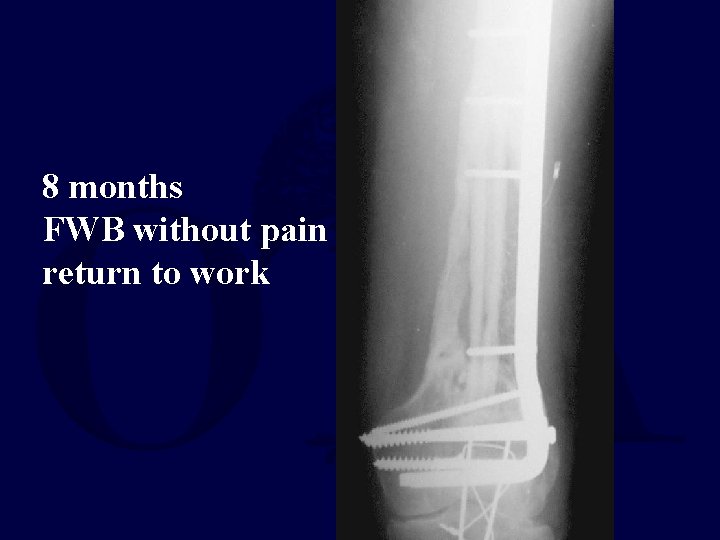

35 yo MVC Open femur with segmental bone loss I&D Ex. Fix Beads

ORIF with bladeplate fibular strut allograft cancellous autograft Ca. SO 4 pellets Bone stimulator

8 months FWB without pain return to work